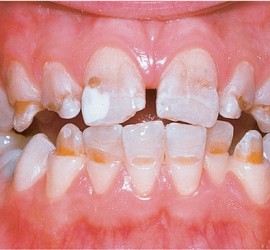

Лечение пульпита. При лечении пульпита перед врачом встают следующие задачи: избавление больного от болевых ощущений, ликвидация инфекционно-токсического очага в пульпе зуба, восстановление формы и функции зуба. Первую помощь больному острым пульпитом может оказать средний медработник или врач любого другого профиля. Она заключается в назначении внутрь обезболивающих препаратов типа анальгина, амидопирина, […]